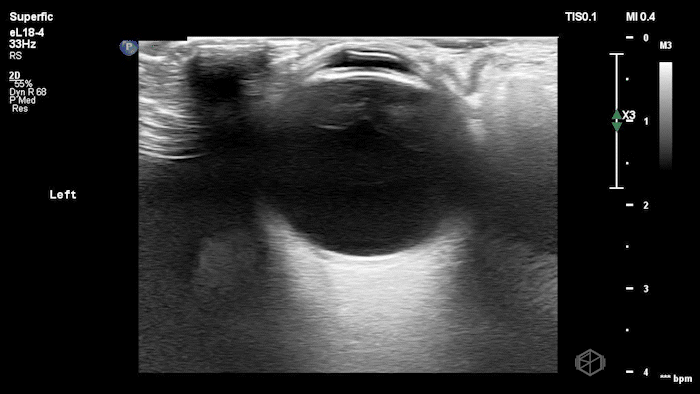

They were examining a 30’s female who was presenting to the ED with headaches for multiple years and had some vision disturbances. The performed an ocular POCUS that demonstrated the following:

The POCUS shows optic nerve edema right (0.793cm) greater than left (0.71cm) with bilateral papilledema. There may also be a faint vitreous detachment of the right eye. There was concerned for increased intracranial pressure.

ONSD measurements in this case are markedly abnormal. The optic nerve sheath diameter (ONSD) is measured 3 mm posterior to the globe. In adults, an ONSD > 5.0 mm is generally considered abnormal; values > 6.0 mm are strongly associated with raised intracranial pressure (ICP). Bilateral measurements of 7.9 mm (right) and 7.1 mm (left) are consistent with elevated ICP. The probe should be held lightly with ample gel to avoid artifactual compression (📚 PMID: 18509619, 18275454)

Point-of-care US measurement of optic disc elevation/height helps when fundoscopy is limited. Studies report cutoffs from ~0.6–1.0 mm: ≥1.0 mm is highly specific for papilledema in ED cohorts; lower cutoffs (≈0.6–0.7 mm) improve sensitivity. (📚 PMID: 24050798, 37227512)